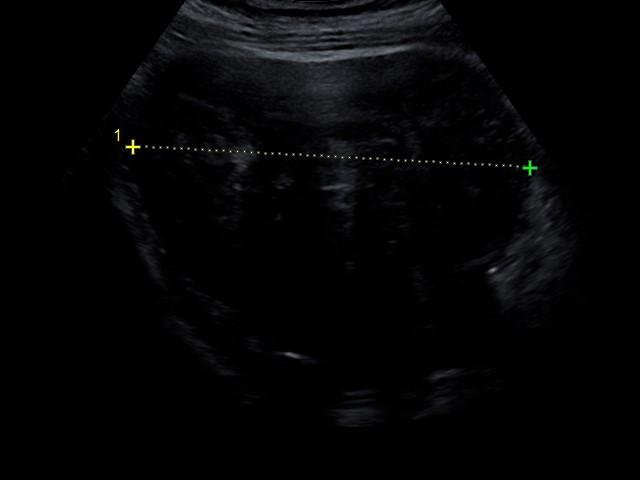

Case Study Comparison

질환별 치료 사례 비교

Before

10cm

After

5cm

자궁근종 (Uterine Myoma)

직경 10cm의 거대 근종이 시술 후 부피 기준 약 90% 소멸되었습니다. 주변 장기 압박으로 인한 빈뇨와 복부 팽만감 증상은 거의 해소되었습니다.